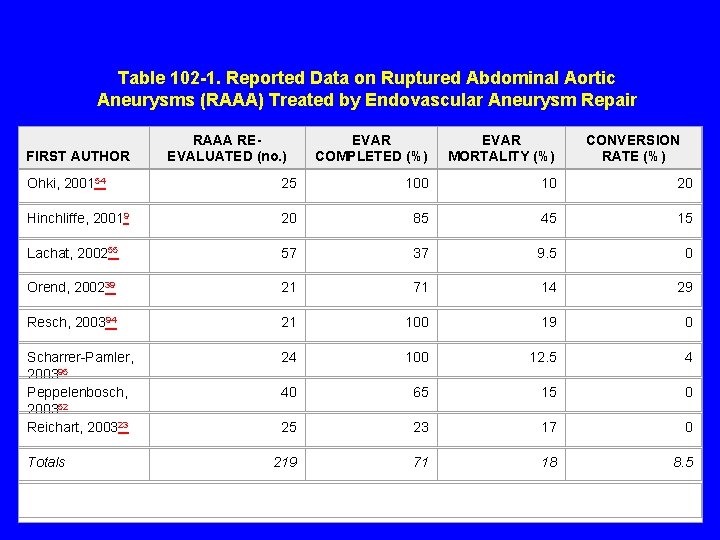

Table 102 -1. Reported Data on Ruptured Abdominal Aortic Aneurysms (RAAA) Treated by Endovascular Aneurysm Repair FIRST AUTHOR RAAA REEVALUATED (no. ) EVAR COMPLETED (%) EVAR MORTALITY (%) CONVERSION RATE (%) Ohki, 200154 25 100 10 20 Hinchliffe, 20019 20 85 45 15 Lachat, 200255 57 37 9. 5 0 Orend, 200239 21 71 14 29 Resch, 200394 21 100 19 0 Scharrer-Pamler, 200395 Peppelenbosch, 200352 Reichart, 200323 24 100 12. 5 4 40 65 15 0 25 23 17 0 219 71 18 8. 5 Totals